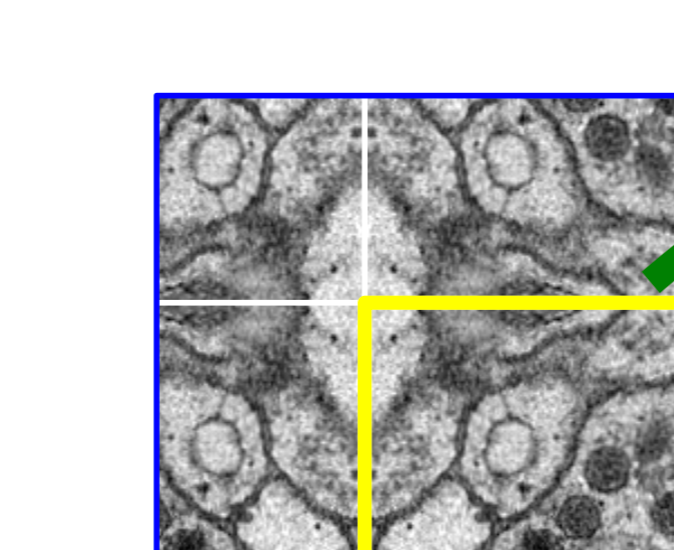

2. Overlap-tile

- U-Net에서 다루는 전자 현미경 데이터의 특성상 이미지 사이즈의 크기가 상당히 크기 때문에 Patch 단위로 잘라서 Input 으로 넣음

- 이때 Fig.2에서 보는 것과 같이 Border 부분에 정보가 없는 빈 부분을 0으로 채우거나, 주변의 값들로 채우거나 이런 방법이 아닌 Mirroring 방법으로 pixel의 값을 채워주는 방법을 사용

- 노랑색 영역이 실제 세그멘테이션 될 영역이고, 파랑색 부분이 Patch

- 거울처럼 반사되어 border부분이 채워짐